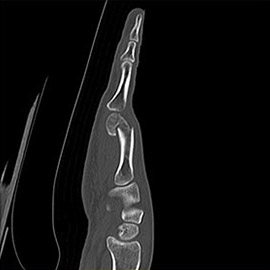

80列マルチスライスCTで撮影した画像

整形